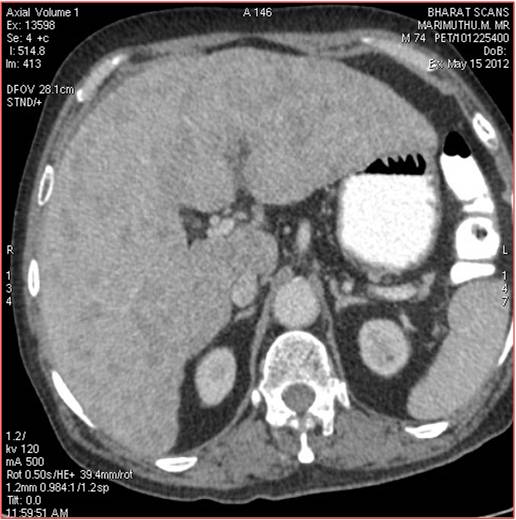

CT scan of the abdomen confirmed the findings ; For further clarification PET whole body scan was done at a centre in Chennai. The following images are from that.

Heterogeneously enhancing irregular spiculated soft tissue mass measuring ~ 34 x 29 mm noted in the apical segment of right upper lobe. The lesion abuts the pleura posteriorly.

Extensive FDG avid hepatic metastases involving both lobes.